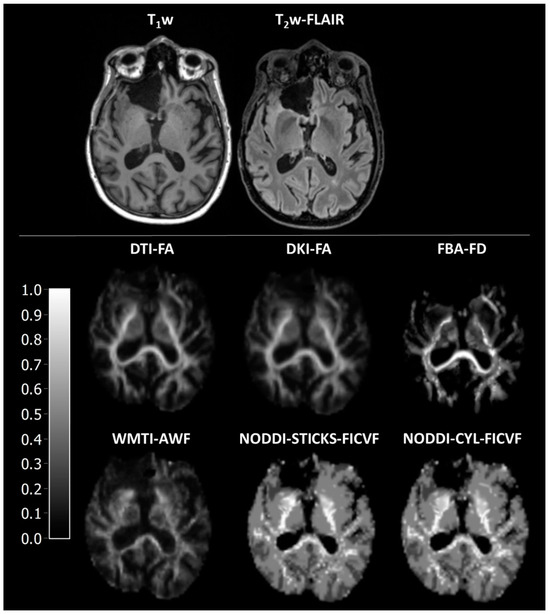

Figure 1. Representative images of axonal fibre-bundle integrity parameters. DTI-FA is fractional anisotropy as estimated using diffusion tensor imaging, DKI-FA is fractional anisotropy as estimated using diffusion kurtosis imaging, FBA-FD is fibre density as estimated using fixel-based analysis, WMIT-AWF is axonal water fraction as estimated with white matter tract integrity, NODDI-STICKS-FICVF is the intracellular volume fraction as estimated using the neurite orientation dispersion and density imaging with the sticks model for neurites, and NODDI-CYL-FICVF is the intracellular volume fraction as estimated using the neurite orientation dispersion and density imaging with the cylinder model for neurites.

As a sanity check to assess whether the various methods displayed discrepant results in correspondence with the different tissue composure, the values of the various parameters were compared between surgical cavity, peri-surgical cavity, NAWM, and WM. As expected, all parameters were significantly different between different tissues (H = 40.4–42.2, p < 0.001, Figure 1 and Figure 2A, Supplementary Tables S1 and S2, Supplementary Figures S1 and S2). Aside from WMTI-IAS-Da, all parameters had a gradient of low/absent in the surgical cavity, higher in peri-surgical cavity, and highest in NAWM and WM (Supplementary Tables S2 and S3).

To determine the agreement between the various DWI methods, the correspondence between them was assessed. All methods strongly correlated with each other (r = 0.77–1.00, Figure 3A, Supplementary Table S4), except for WMTI intra-axonal diffusivity (r = 0.05–0.30). Furthermore, a low bias as depicted by differences in slope and ICC was observed (Figure 3A and Supplementary Table S5) between DTI-FA, DKI-FA, WMTI-AWF, and FBA-FD, and between NODDI-STICKS-FICVF and NODDI-CYL-FICVF, but with a high bias between the two groups. When compared to each other, the methods were significantly different from each other at a group level (H = 9609, p < 0.001, Table 3, Supplementary Tables S2 and S6). Bonferroni-corrected post hoc tests showed that all were different except for DTI-FA from DKI-FA (H = 126, p = 1.000), NODDI-CYL-FICVF from NODDI-STICK-FICVF (H = 162, p = 1.000), and DKI-FA from WMTI-AWF (H = −357, p = 0.076), as determined via Bonferroni-corrected post hoc tests. These findings suggest that while the absolute values were statistically different from each other, the relative change in parameters between the different ROIs was similar for all axonal fibre-bundle integrity parameters (except WMTI-IAS-Da).

In general, the different DWI models have a high correspondence with each other, as displayed by the strong correlations. The only discrepant result is in this case WMTI-IAS-Da, which is the intra-axonal diffusivity. This parameter is high in the surgical cavity, medium-high in the peri-surgical cavity, and low in the NAWM and WM. As this parameter is supposed to depict the diffusivity within axons, and no axons are present in the surgical cavity, and there is a high abundance in the WM, this finding is rather unexpected. In the documentation of PyDESIGNER, there is no information regarding the calculations of WMTI [28], and neither is there in the original DESIGNER article [31]. However, in the DESIGNER article, the authors cite Fieremans et al. for the WMTI model [11,31]. Therefore, we assume that the developers of PyDESIGNER used the Fieremans model. In the study of Fieremans et al., WMTI-IAS-Da is the trace of the intra-axonal diffusivity, thus the summation of the intra-axonal eigenvalues [11]. While the article of Fieremans shows similar patterns of WMTI-AWF and WMTI-IAS-Da, this correspondence is clearly absent in the results of PyDESIGNER. This difference suggests an erroneous implementation of the WMTI-IAS-Da calculation in PyDESIGNER (Supplementary Figures S1 and S2). Surprisingly, WMTI-AWF generated with PyDESIGNER corresponds with physiological expectations and also with axonal fibre-bundle integrity parameters derived from other DWI models (Figure 1 and Figure 2).